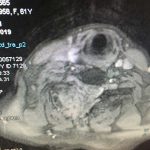

Εικόνα 4: Μαγνητική Τομογραφία (31.10.2018) της Οσφυϊκής και Ιερής περιοχής της Σπονδυλικής Στήλης.

Οβελιαία Λήψη – Ακολουθία Τ2. Παρατηρείται η ύπαρξη μεταστάσεων στον 1-2 Ιερό σπόνδυλο – λαγόνιο (Αρ) Οστούν.